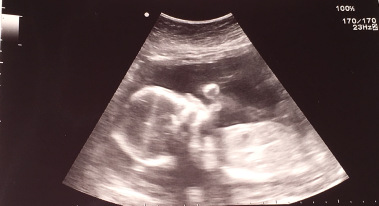

But the thing is, I’m now pregnant. 26 weeks to be exact. With this darling, sweet little angel GIRL!

You have to admit, she’s already adorable, isn’t she?